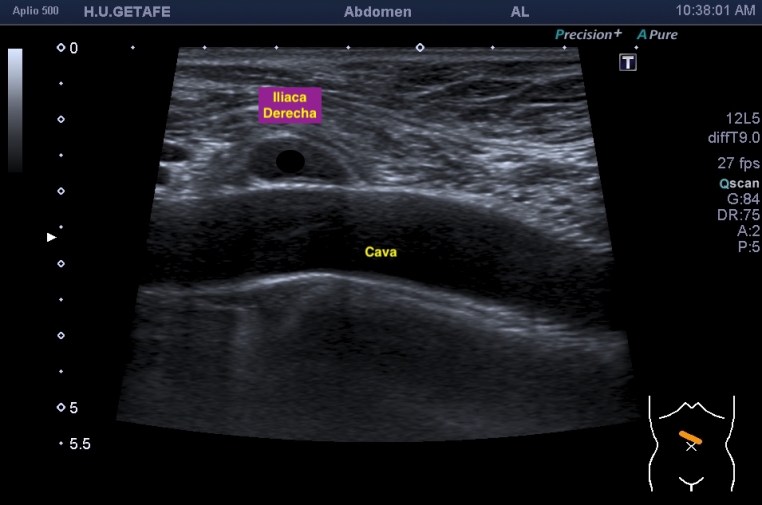

Lo que ves en estas imágenes que te voy a poner aquí son los hallazgos ecográficosque he podido visualizar hoy. Los voy a complementar con la correlación con las imágenes de TAC. En este caso específico con la eco solo se pudo corroborar los hallazgos del escáner, que a nivel anatómico arroja un mejor desarrollo de la anatomía regional implicada en el proceso.

6En el corte longitudinal de la imagen 1 ya se ve una vaso perimetrado por una imagen hiperecogénica, no compresible a la presión con la sonda convexa. En la imagen 2 con la sonda lineal se observa el enrejado habitual de los stents, que en otras ocasiones ya hemos comentado en otro post en localización distinta.

En el corte axial de las imágenes 3 y 4 puedes ver la anatomía radiológica implicada. La relación es perfecta, y completamente explicativa de la situación resulta mediante el tratamiento quirúrgico. En ella la Arteria iliaca derecha para justo por encima de la Vena iliaca Izquierda con la capacidad de poder comprimirla.